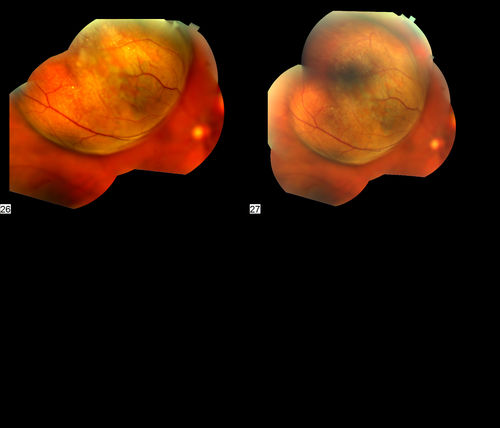

Malignant Melanoma

60 year old woman presents with obscured vison in the right eye. Diagnosed with Malignant Melanoma.

Kathy Karsten, COT. Retina Specialists of Michigan

Fundus Camera Topcon TRX-50DX